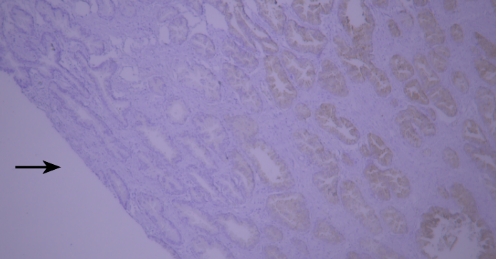

1 人淋巴结组织石蜡切片CD45染色:因组织固定不充分,淋巴结边缘淋巴细胞CD45染色强阳性,组织内部淋巴细胞染色弱阳性,整体染色不均。

典型实例:人结肠癌石蜡组织切片CEA染色,出现染色液堆积(黑色箭头区域)。

典型实例:人扁桃体石蜡组织切片Lysozyme染色,因边缘效应出现非特异性染色(黑色箭头区域)。